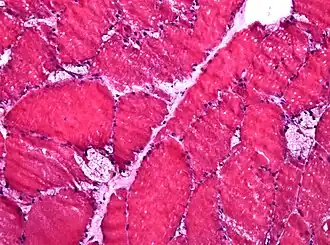

![]() Биопсия мышечной ткани: на замороженном микропрепарате видны крупные вакуоли, характерные для болезни Помпе | |

- морфологический анализ мышечной ткани (биопсия) позволяет выявить специфические изменения, однако их отсутствие не исключает наличия болезни Помпе.